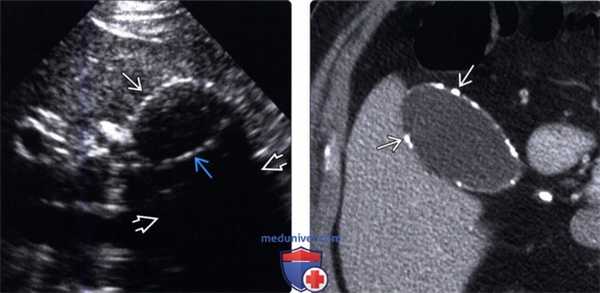

(Левый) Пример неполного кальциноза: у женщины 67 лет, жалующейся на боли в правом верхнем квадранте живота после еды определяются отдельные гиперэхогенные очаги передней и задней стенок желчного пузыря, отбрасывающие неоднородную тень.

(Правый) Пример неполного кальциноза: у мужчины 61 года в стенке желчного пузыря визуализируются точечные кальцинаты. Выявленные при патологоанатомическом исследовании конкременты не визуализируются.